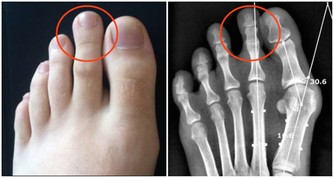

太沖:大腳趾和二腳趾指縫之間上面1寸,是肝經的原穴。揉太沖穴可以給心臟供血,對情緒壓抑有宣泄作用。是肝經的原穴。推太沖穴的時候會覺得太沖穴很痛,就證明你肝氣有郁結,你給它推到不痛了,推到行間穴痛了,肝臟的郁結就消散了,而且肝血就源源不斷的供應到心臟去了,心臟血液就供應充足了,所以這個穴非常重要,這兩個穴配合起來效果是最好的。太沖穴在大趾和二趾縫隙間,是在骨縫裏邊,這個穴很深,需要把指甲剪平,然後用掐的方法,才能揉到這個穴。必須用掐的方法,揉到這個穴以後往下搟,一直把這個痛點搟到行間去,當痛點轉移了,太沖不痛了,行間痛了,這個初步的操作方法已經完成了。

行間:大腳趾和二腳趾指縫之間。配合太沖穴向行間方向推,可起到消除肝臟郁積的作用,使肝血源源不斷地供到心臟。